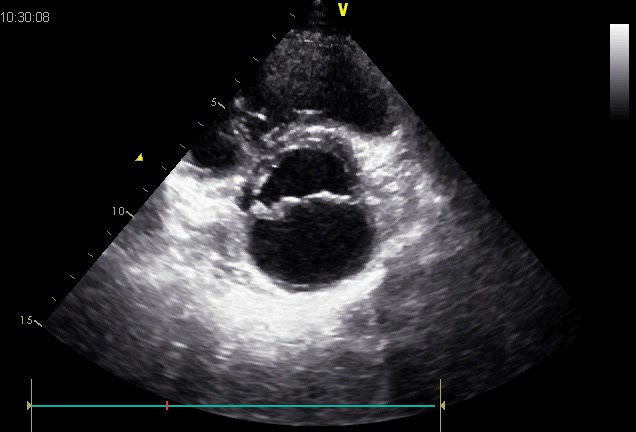

胸骨旁大动脉短轴切面